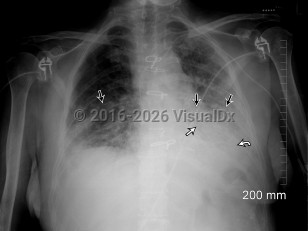

COVID-19